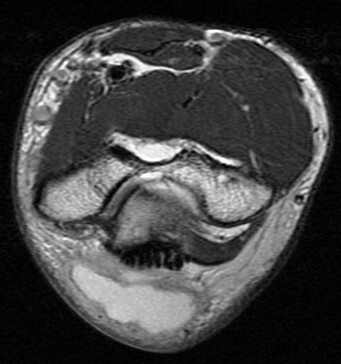

Figure 4 for case olecranon bursitis ( RID2082 )

Figure 4

Fluid and bursal lining thickening. Area edema. This was non septic. No osteomyelitis. Reference article.

olecranon bursitis ( RID2082 )